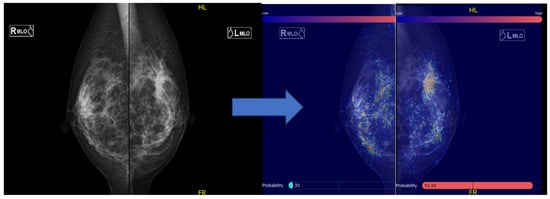

We used the MG AI system FxMammo® (FathomX Pte Ltd., Singapore). The AI system is based on deep learning and has been put into practical use in Singapore and other countries. The mechanism of FxMammo has been described in previous studies. The AI system is based on the VGG-16 network [20]. The VGG network is one of the most used feature extractors in medical imaging classification [21]. The AI was created by collecting 17,769 cases (of which 45% were malignant) from 10 institutions in Taiwan, Thailand, Singapore, Hong Kong, China, Malaysia, and Japan. Since 2019, we have been collaborating with the National University of Singapore to develop MG AI for Asian women. This AI model, which utilizes CNNs and graph convolutional networks, quantifies the probability of malignancy and highlights areas of interest on a heat map when mammography images are uploaded. The model demonstrated a high Area Under the Curve (AUC) of 0.902 for BC detection [22]. If we assume a cancer miss rate of 3%, it is estimated that up to 38% of normal MG could be safely excluded from human review. In Japan, the AI system has not been approved for clinical use and it is used for research purposes. Four MG images (craniocaudal [CC], mediolateral oblique [MLO], left, and right) taken before surgery for heterochronic contralateral BC were transferred from the reporting system to the AI system where the MG data were analyzed. The threshold value was set to 40.0%, (91.5% sensitivity and 82.0% specificity). The AI system indicated the probability of malignancy for each of the four cards as a percentage. In addition, areas in which the AI system was interested were displayed in color on a heat map. The areas on which the AI system focused when analyzing the image are visually shown as a heat map (Figure 2).

Figure 2.

Displaying images in FxMammo. An image of the mediolateral oblique of mammography is shown on the left. A spiculated mass is seen in the left upper area. On the right is the result of the AI system analysis, with the areas of interest to the AI system indicated by the colors in the heatmap. The malignancy percentage is shown on the left and right sides, respectively (right: 3.3%; left: 94.2%).